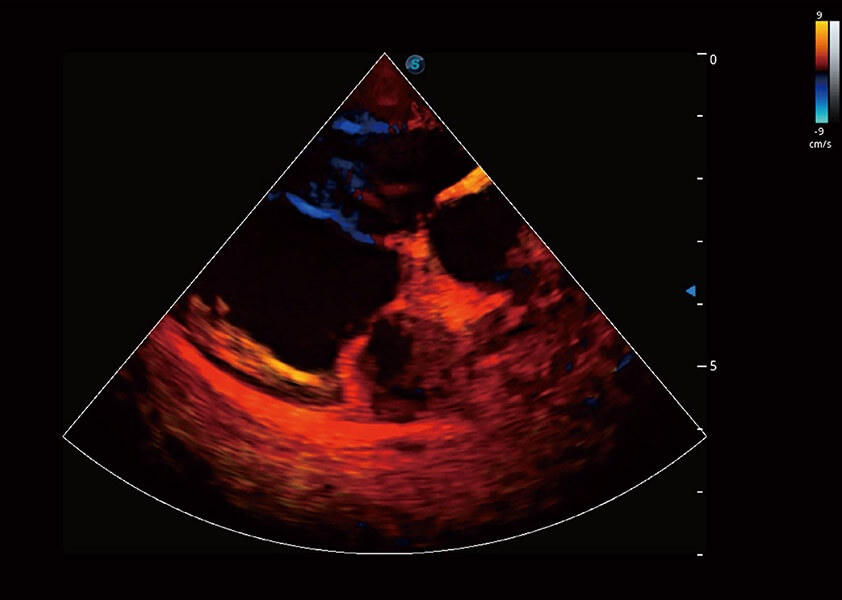

(犬)心脏组织多普勒